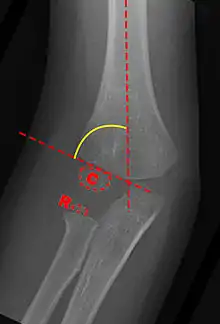

Anterior X-ray

Carrying angle can be evaluated through AP view of the elbow by looking at the Baumann’s angle.[2] There are two definitions of Bowmann's angle:

The first definition of Baumann's angle is an angle between a line parallel to the longitudinal axis of the humeral shaft and a line drawn along the lateral epicondyle.

Another definition of Baumann's angle is also known as the humeral-capitellar angle. It is the angle between the line perpendicular to the long axis of the humerus and the growth plate of the lateral condyle. Reported normal values for Baumann's angle range between 9 and 26°.[5] An angle of more than 10° is regarded as acceptable.[5]